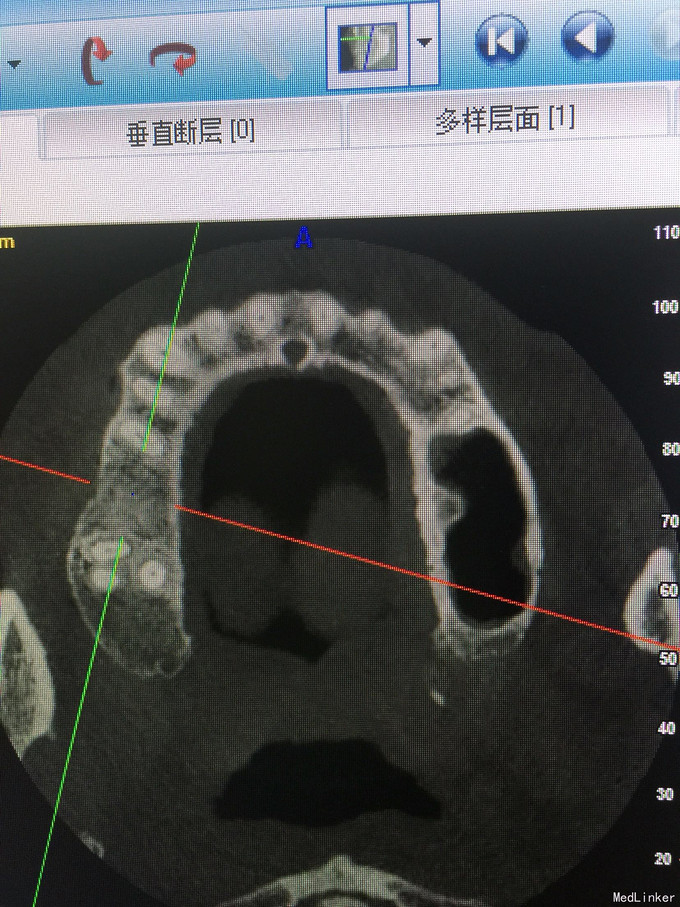

张先生,右上6缺失多年,要求种植

骨量只有2.4毫米

上颌窦内提,同期植入4.1-10植体